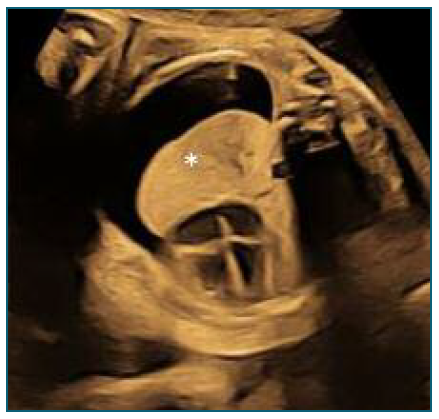

The shunt placement, at 32 weeks and 3 days (Figure 2), occurred without complications, although laborious due to fetal positioning, pleural fluid was collected for analysis. The shunt appeared to be functioning with clear improvement in effusion (Figure 3).